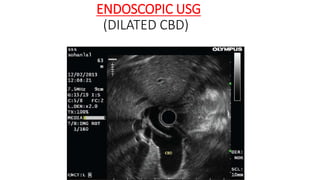

ENDOSCOPIC USG

• EUS has been reported to have up to a 98%

diagnostic accuracy in patients with

obstructive jaundice.

• Allows diagnostic tissue sampling via EUS-

guided fine-needle aspiration (EUS- FNA).

• The sensitivity of EUS for the identification

of focal mass lesions in pancreas has been

reported to be superior to that of CT

scanning particularly for tumors smaller

than 3 cm in diameter.

• Compared to MRCP for the diagnosis of

biliary stricture, EUS has been reported to

be more specific (100% vs. 76%) and to

have a much greater positive predictive

value (100% vs. 25%), although the two

have equal sensitivity (67%).

(DILATED CBD)